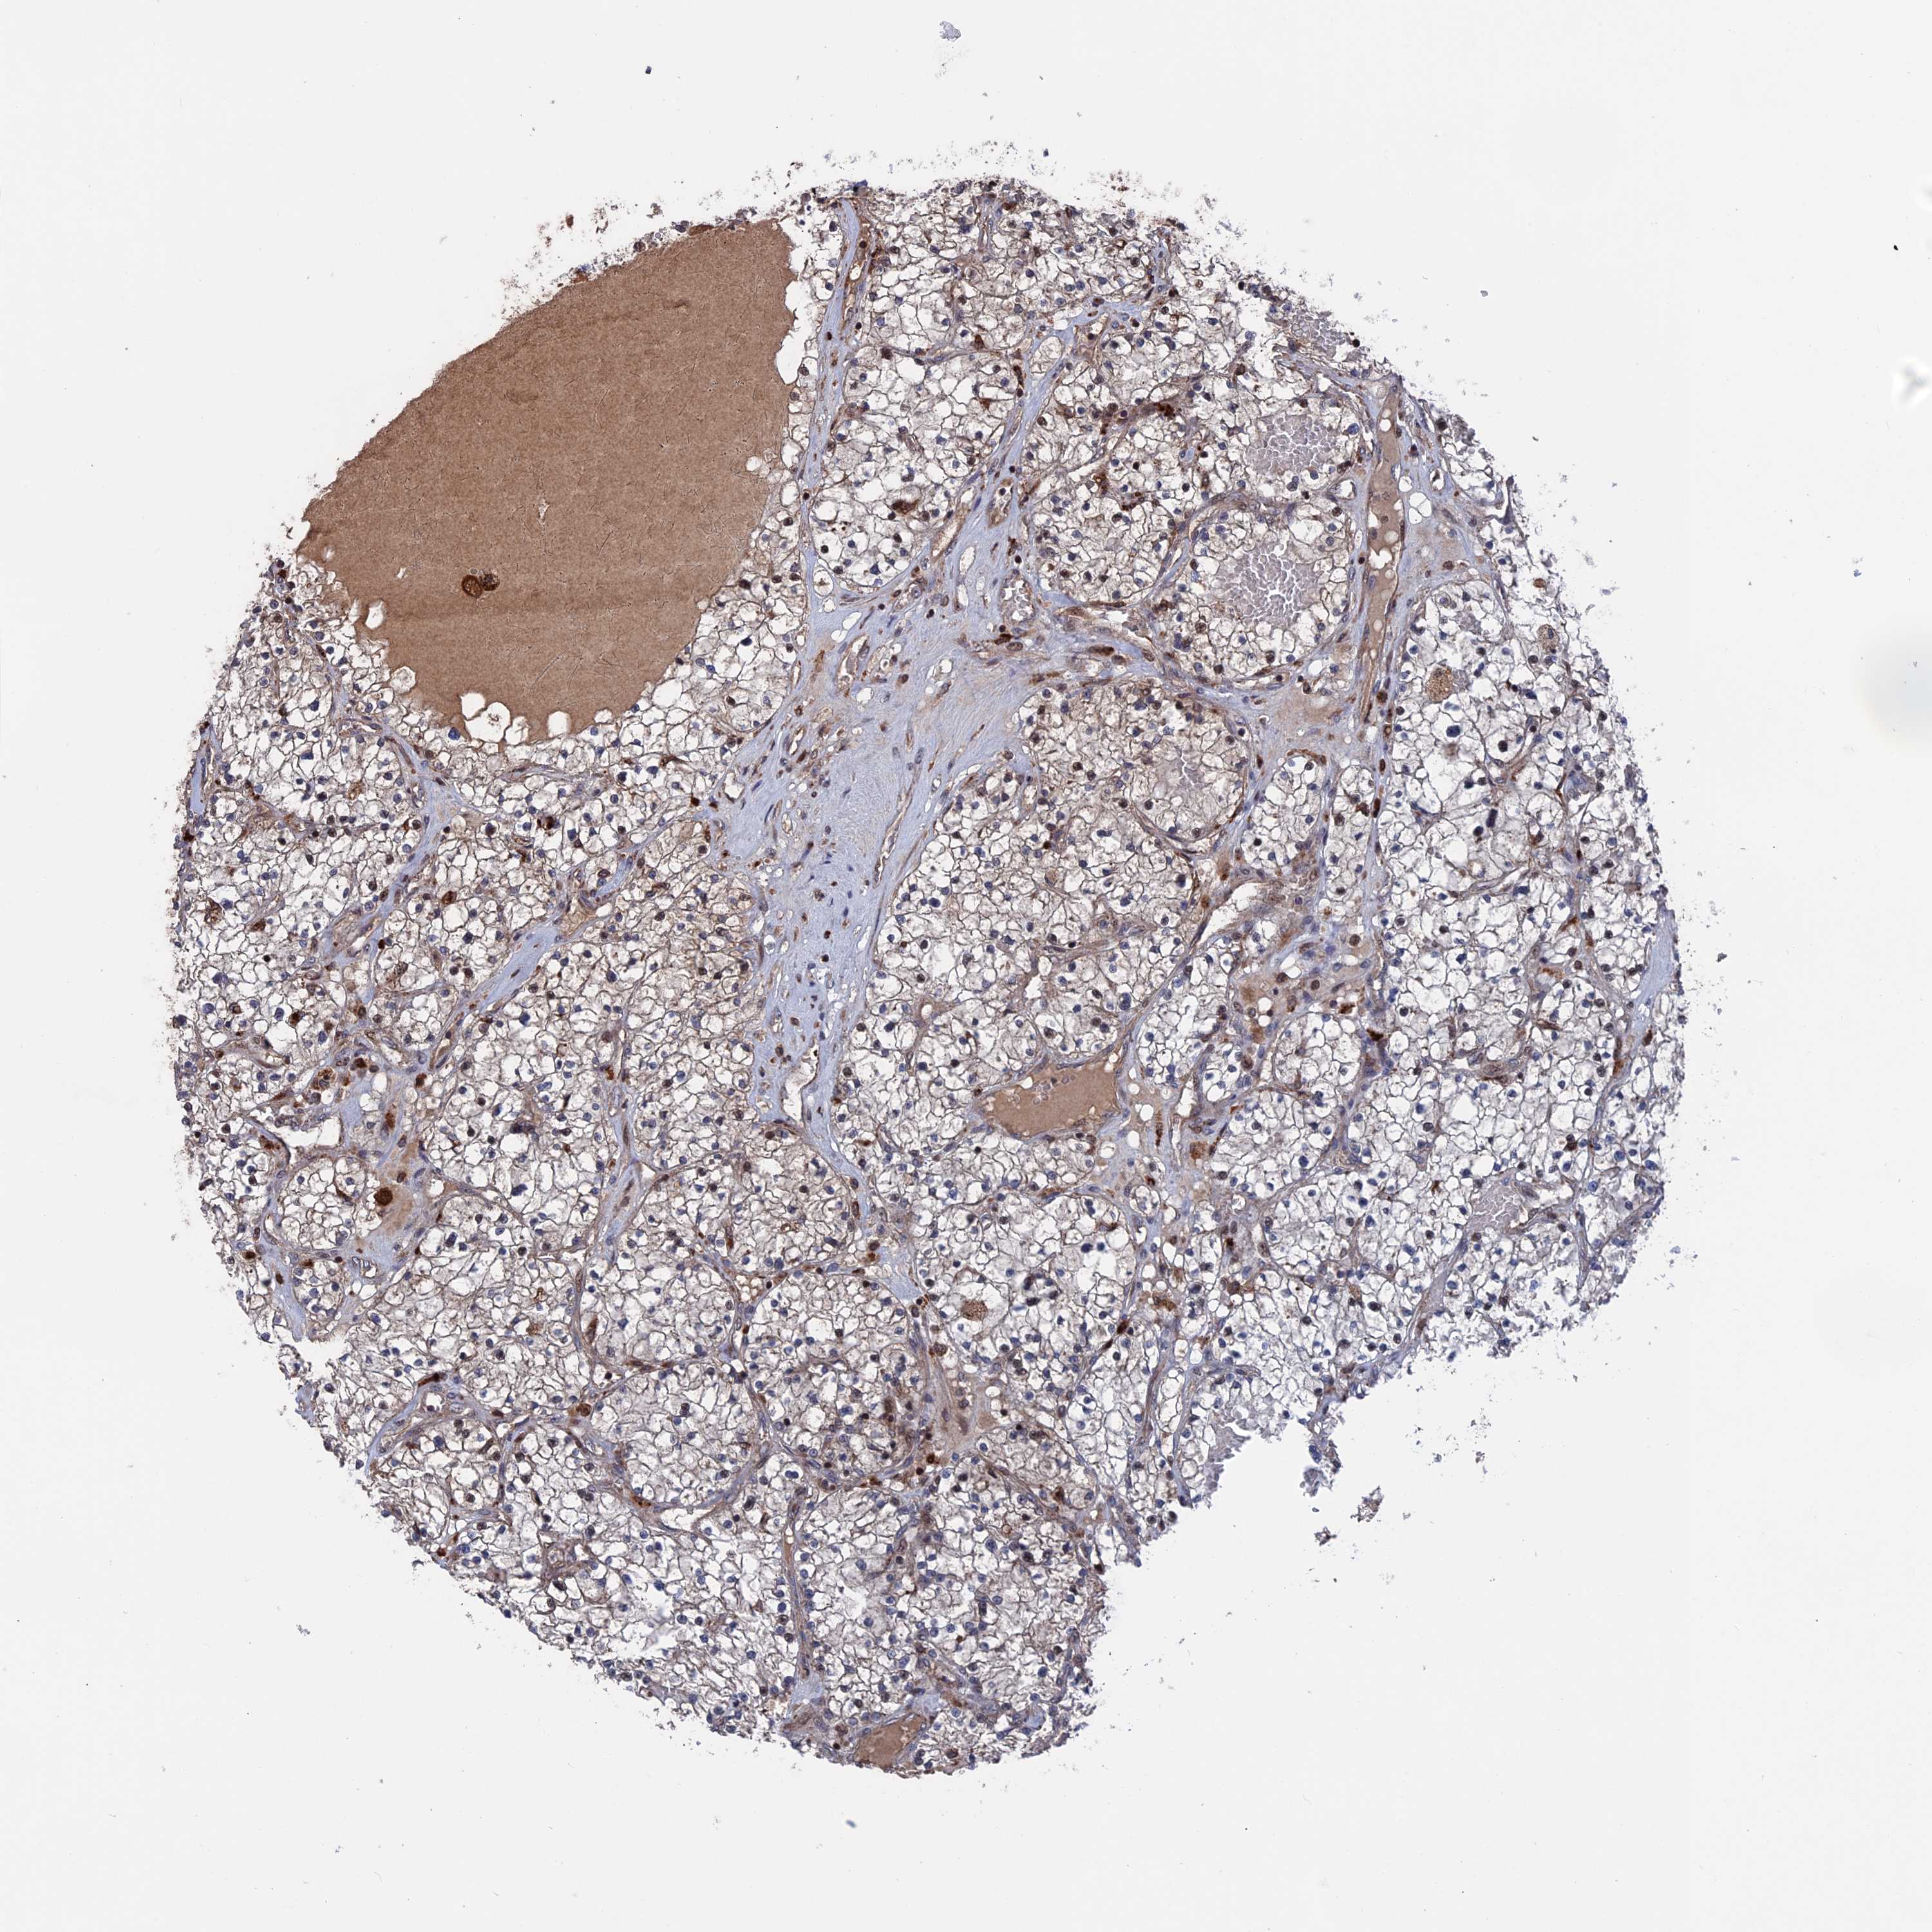

KIDNEY RENAL PAPILLARY CELL CARCINOMA (TCGA) - Interactive survival scatter ploti

The Survival Scatter plot shows the clinical status (i.e. dead or alive) for all individuals in the patient cohort, based on the same data that underlies the corresponding Kaplan-Meier plots. Patients that are alive at last time for follow-up are shown in blue and patients who have died during the study are shown in red.

The x-axis shows the expression levels (FPKM) of the investigated gene in the tumor tissue at the time of diagnosis. The y-axis shows the follow-up time after diagnosis (years). Both axes are complimented with kernel density curves demonstrating the data density over the axes. The top density plot shows the expression levels (FPKM) distribution among dead (red) and alive patients (blue). The right density plot shows the data density of the survived years of dead patients with high and low expression levels respectively, stratified using the cutoff indicated by the vertical dashed line through the Survival Scatter plot. This cutoff is automatically defined based on the FPKM cutoff that minimizes the p-score. The cutoff can be changed by dragging the vertical line or by entering a cutoff value in the square labeled "Current cut-off".

Under the Survival Scatter plot the p-score landscape (black curve; left axis) is shown together with dead median separation (red curve; right axis). Dead median separation is the difference in median mRNA expression between patients who have died with high and low expression, respectively. It is calculated as follows: median FPKM expression of dead patients with high expression - median FPKM expression of dead patients with low expression. This is intended to aid the user in visually exploring custom cutoffs and the associated p-scores and dead median separation.

Individual patient data is displayed and can be filtered by clicking on one or more of the category buttons on the top of the page. Categories describing expression level and patient information include: high, low, alive, dead, female, male and tumor stages. The scale of the x-axis can be toggled between linear and log-scale by clicking on the "x log" button. Mouse-over function shows TCGA ID, patient information and mRNA expression (FPKM) for each patient.

& Survival analysisi

Kaplan-Meier plots summarize results from analysis of correlation between mRNA expression level and patient survival. Patients were divided based on level of expression into one of the two groups "low" (under cut off) or "high" (over cut off). X-axis shows time for survival (years) and y-axis shows the probability of survival, where 1.0 corresponds to 100 percent.

PLA2G15 is not prognostic in Kidney Renal Papillary Cell Carcinoma (TCGA)

Best expression cut offi

Based on the FPKM value of each gene, patients were classified into two groups and association between prognosis (survival) and gene expression (FPKM) was examined. The best expression cut-off refers the FPKM value that yields maximal difference with regard to survival between the two groups at the lowest log-rank P-value. Best expression cut-off was selected based on survival analysis .

When clicking on this number, the vertical dashed line indicating cut-off, the interactive survival plot, and the Kaplan-Meier curve will be adjusted to show results based on the best expression cut-off.

: 28.35